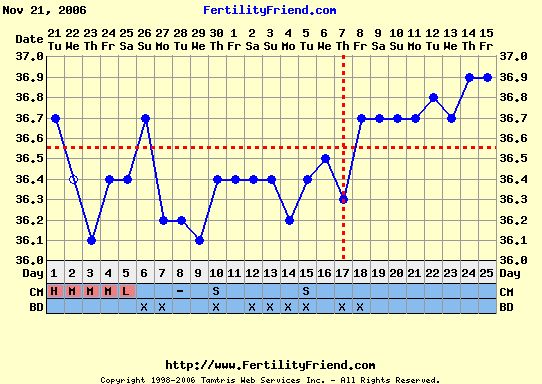

Éva, ez aztán a szép görbe! Igaz, én kicsi meglepődtem, hogy a 10. napon volt a pé-ed, de mivel nem esik vissza, tényleg akkor lehetett. Akkor viszont nemsokára tesztelhetsz!

Verzsike, szerintem ebből a görbéből még akármi lehet. A legjobb egy + volna a tesztek sávjában!

Ez a leesés akár beágyazódás is lehetett!!!

Addig is a semleges görbém.